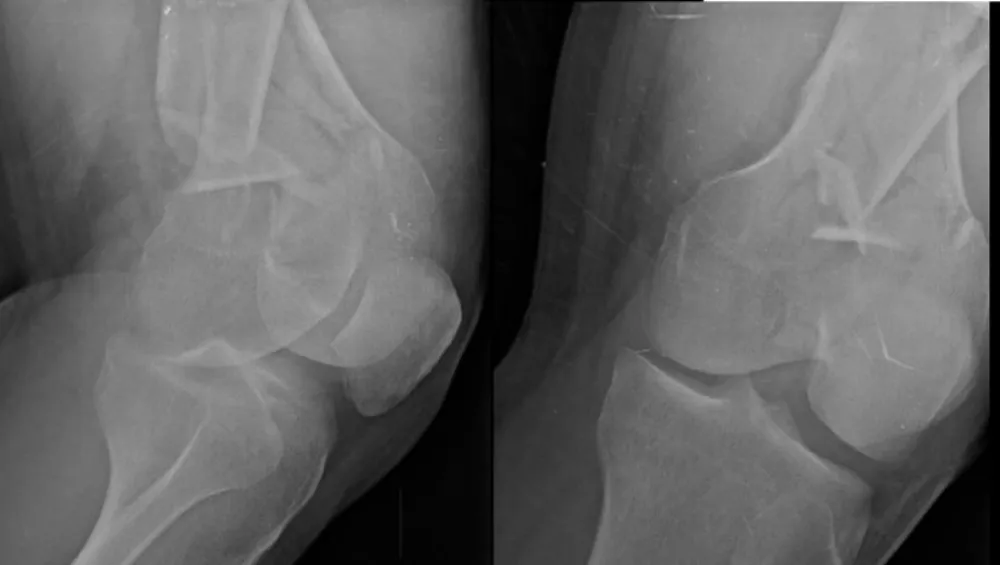

Figure 2: Pre-operative imaging of distal femur fractures. Representative lateral views demonstrate bilateral open distal femur fractures (right Gustilo‑Anderson II; left I).

Figure 3: Additional pre-operative oblique/lateral projections detailing comminution and distal extension.